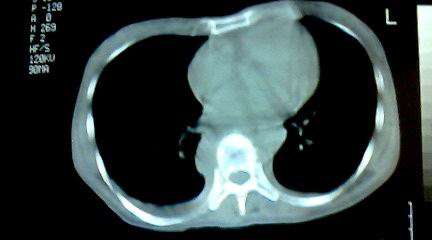

标题: CT25218:请教!胸部CT,胸8椎体骨质破坏,伴周围软组织肿。 [打印本页]

标题: CT25218:请教!胸部CT,胸8椎体骨质破坏,伴周围软组织肿。

患者,女41岁,肢体乏力。

两肺上叶继发性肺结核;胸椎结核并椎旁寒性脓肿形成。

胸椎结核并椎旁寒性脓肿形成。